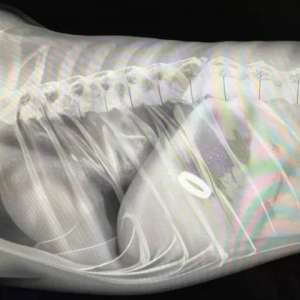

14 февраля в Челябинске пёс Беляш, вероятно, съел кольцо, которое молодой человек приготовил для предложения своей девушке.

Однако юноша не пал духом и попросил ветеринара внести в справку о состоянии здоровья собаки «специальную рекомендацию» — ответить «да» на его предложение.